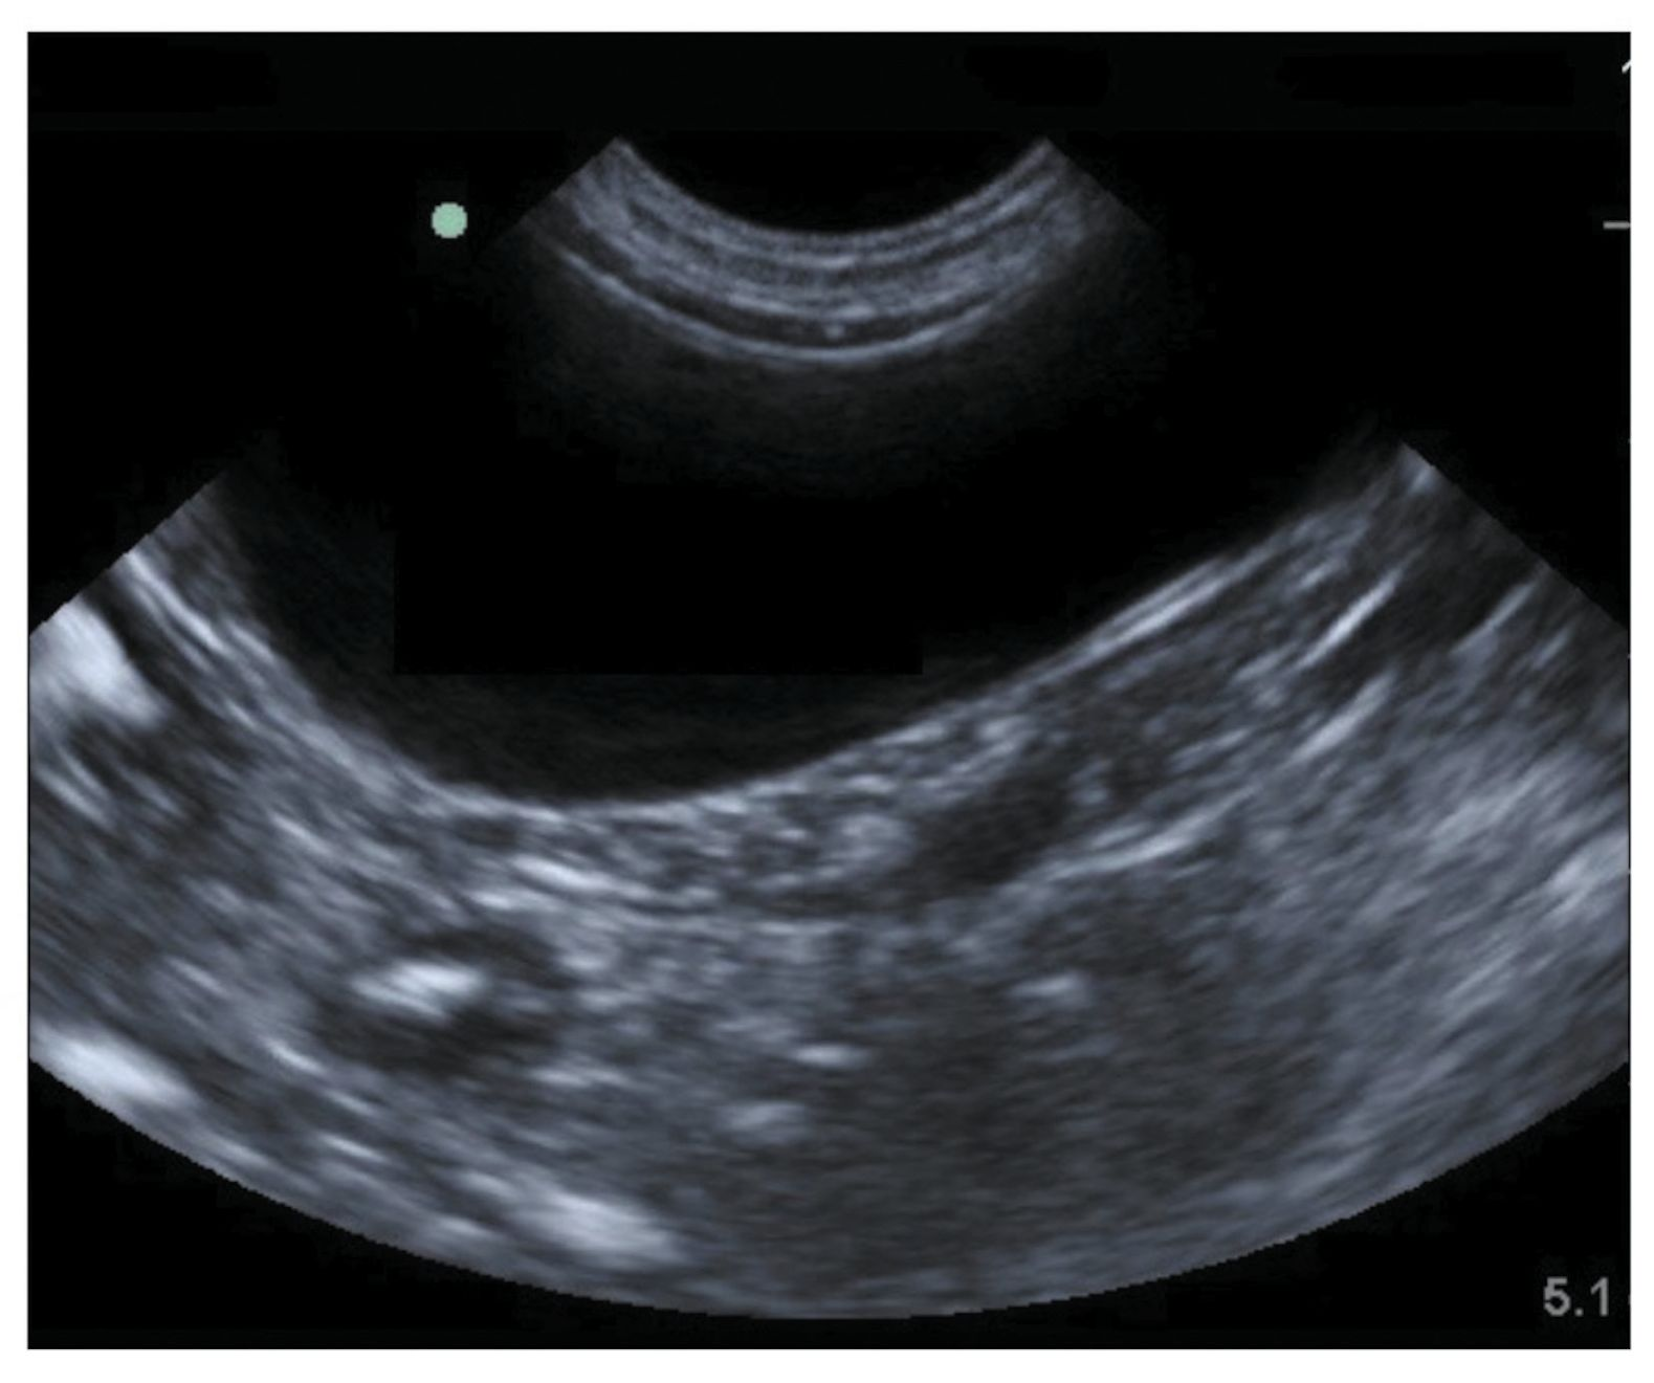

Sagittal image of the urinary bladder of Cat 1. In males the inferior surface of the bladder lays over the pubic symphysis and prostate posteriorly is the distal third of the rectumBetween the posterior surface of the. Describe the wall of the urinary bladder of the fetal pig.

Sagittal Image Of The Urinary Bladder Of Cat 1 Note The Dependently Download Scientific Diagram